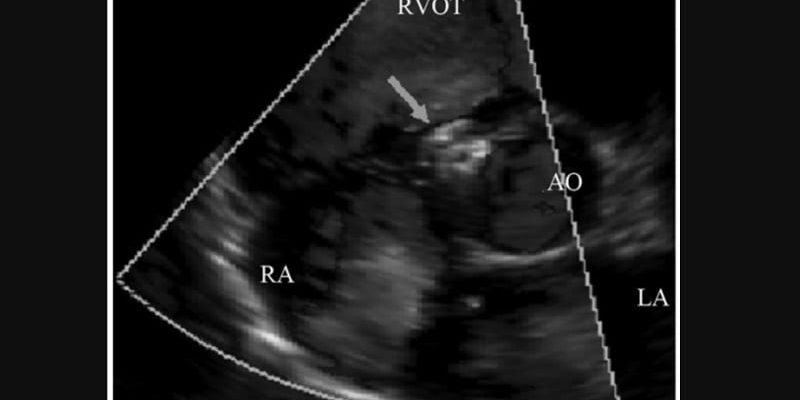

San Francisco – In der ersten randomisierten kontrollierten Studie mit dem TriClip Transcatheter Tricuspid Valve Repair System (Abbott) zur Transkatheter-Edge-to-Edge-Reparatur (TEER) der Trikuspidalklappe bei Patienten mit schwerer Trikuspidalinsuffizienz (TR) zeigten die Patienten eine anhaltende ...